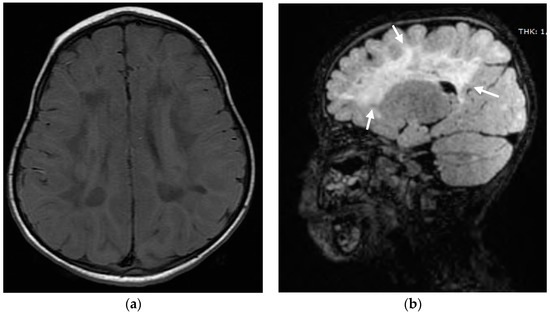

2. Case Report